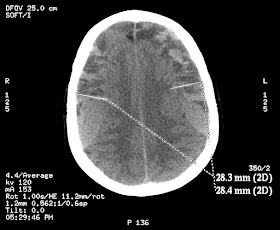

Con

la sospecha clínica de una posible hematoma intracraneal se realizó

de forma urgente un  TAC cerebral sin CIV que mostró lo siguiente:

Extensas

colecciones extraaxiales bilaterales en la convexidad

frontoparietotemporal, de aprox 2,8 cm de espesor máximo, con áreas

hipodensas e  hiperdensas formando nivel. Efecto masa con borramiento

de surcos de la convexidad y colapso parcial del sistema ventricular

supratentorial. Línea media centrada.

¡Todo

ello compatible con el diagnóstico de hematomas subdurales crónicos

con componente agudo!